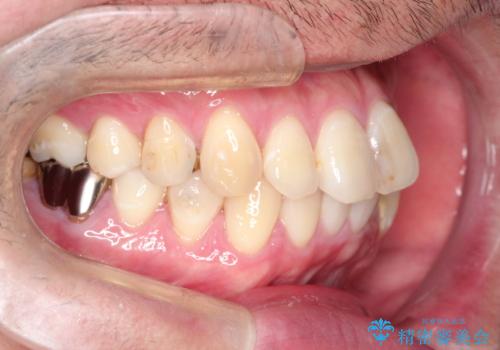

全体的ながたつきをインビザラインで改善

- 全体的ながたつきを主訴に来院されました。

歯と歯の間をわずかに削って、スペースをつくり並べる計画としました。

しっかりと、マウスピースの装着時間を守っていただいたので、スムーズに治療をおえることができました。